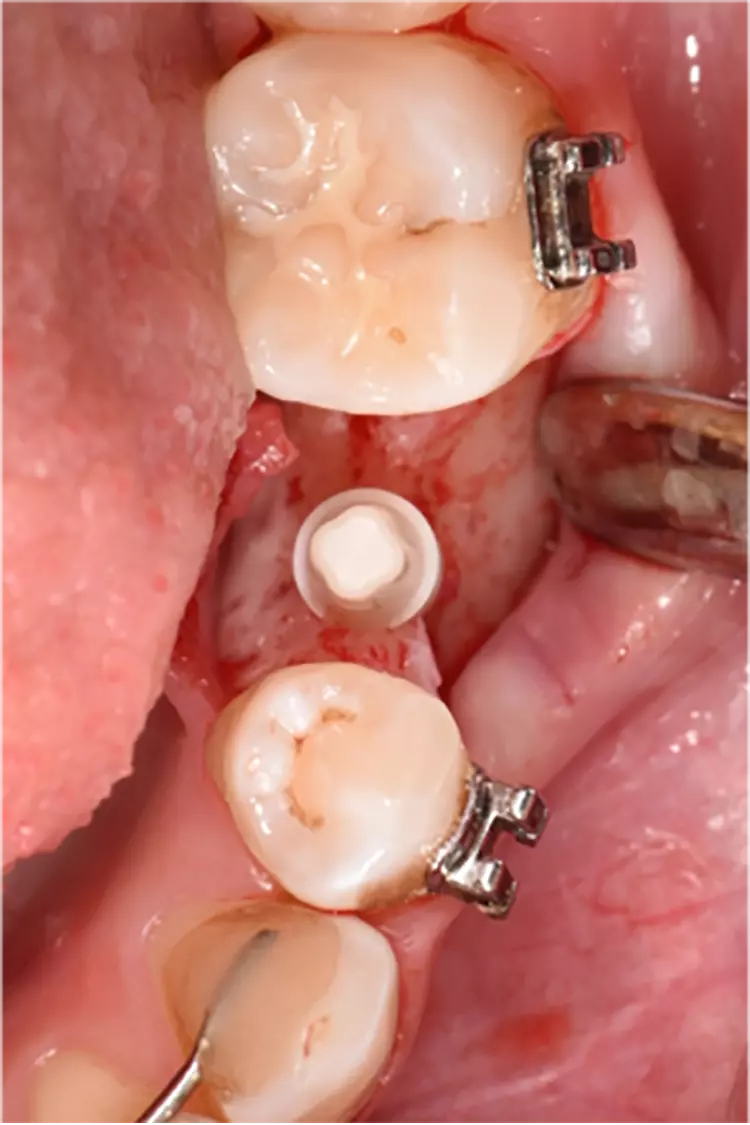

Die Implantate wurden im üblichen chirurgischen Vorgehen inseriert und sofort mit einem Provisorium aus Polymethylmethacrylat (CAD-Temp, VITA) versorgt, wobei die Provisorien außer Okklusion geschliffen wurden und darauf geachtet wurde, dass approximal nur sehr schwache Kontakte bestanden (Abb. 3a bis e). Die definitive prothetische Versorgung erfolgte im Unterkiefer nach frühestens 2 Monaten, im Oberkiefer nach frühestens 4 Monaten. Die Restaurationen wurden aus verblendetem Zirkonoxid hergestellt (VITA YZ HT / VITA VM 9, VITA).

Bei Knochendefekten ist eine Augmentation erforderlich. In der klinischen Studie „FR/ZH“ wurden in 11 Fällen kleinere simultane Augmentationen durchgeführt (vergl. Abb. 3). Die Augmentationen dürfen aufgrund der ermittelten Sondiertiefen und Röntgenbefunde als erfolgreich angesehen werden.